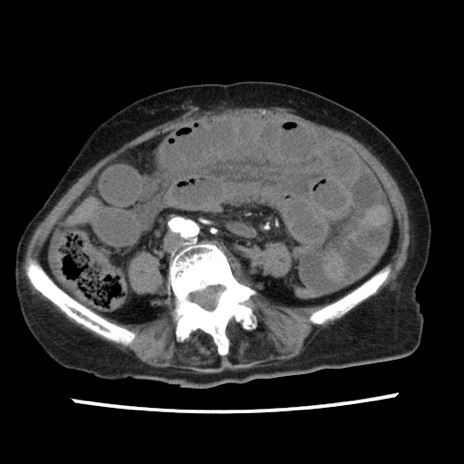

症例1(横断像)

【症例】80歳代女性

【主訴】腹痛

【現病歴】8時間前から腹痛あり来院。

【既往歴】糖尿病、脂質異常症、子宮体癌にて子宮全摘術

【身体所見】意識清明・会話良好だが腹痛で苦悶様、全腹部にわたって反跳痛と圧痛あり

【データ】WBC 13600、CRP 0.14、LDH 224、CK 90